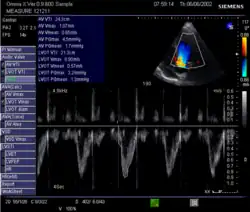

Doppler ultrasound

Doppler signal in the left ventricular outflow tract: Velocity Time Integral (VTI)

This method uses ultrasound and the Doppler effect to measure cardiac output. The blood velocity through the heart causes a Doppler shift in the frequency of the returning ultrasound waves. This shift can then be used to calculate flow velocity and volume, and effectively cardiac output, using the following equations:

where:

• CSA is the valve orifice cross sectional area,

• r is the valve radius, and,

• VTI is the velocity time integral of the trace of the Doppler flow profile.

Being non-invasive, accurate and inexpensive, Doppler ultrasound is a routine part of clinical ultrasound; it has high levels of reliability and reproducibility, and has been in clinical use since the 1960s.

Echocardiography is a non-invasive method of quantifying cardiac output using ultrasound. Two-dimensional (2D) ultrasound and Doppler measurements are used together to calculate cardiac output. 2D measurement of the diameter (d) of the aortic annulus allows calculation of the flow cross-sectional area (CSA), which is then multiplied by the VTI of the Doppler flow profile across the aortic valve to determine the flow volume per beat (stroke volume, SV). The result is then multiplied by the heart rate (HR) to obtain cardiac output. Although used in clinical medicine, it has a wide test-retest variability.[9] It is said to require extensive training and skill, but the exact steps needed to achieve clinically adequate precision have never been disclosed. 2D measurement of the aortic valve diameter is one source of noise; others are beat-to-beat variation in stroke volume and subtle differences in probe position. An alternative that is not necessarily more reproducible is the measurement of the pulmonary valve to calculate right-sided CO. Although it is in wide general use, the technique is time-consuming and is limited by the reproducibility of its component elements. In the manner used in clinical practice, precision of SV and CO is of the order of ±20%.